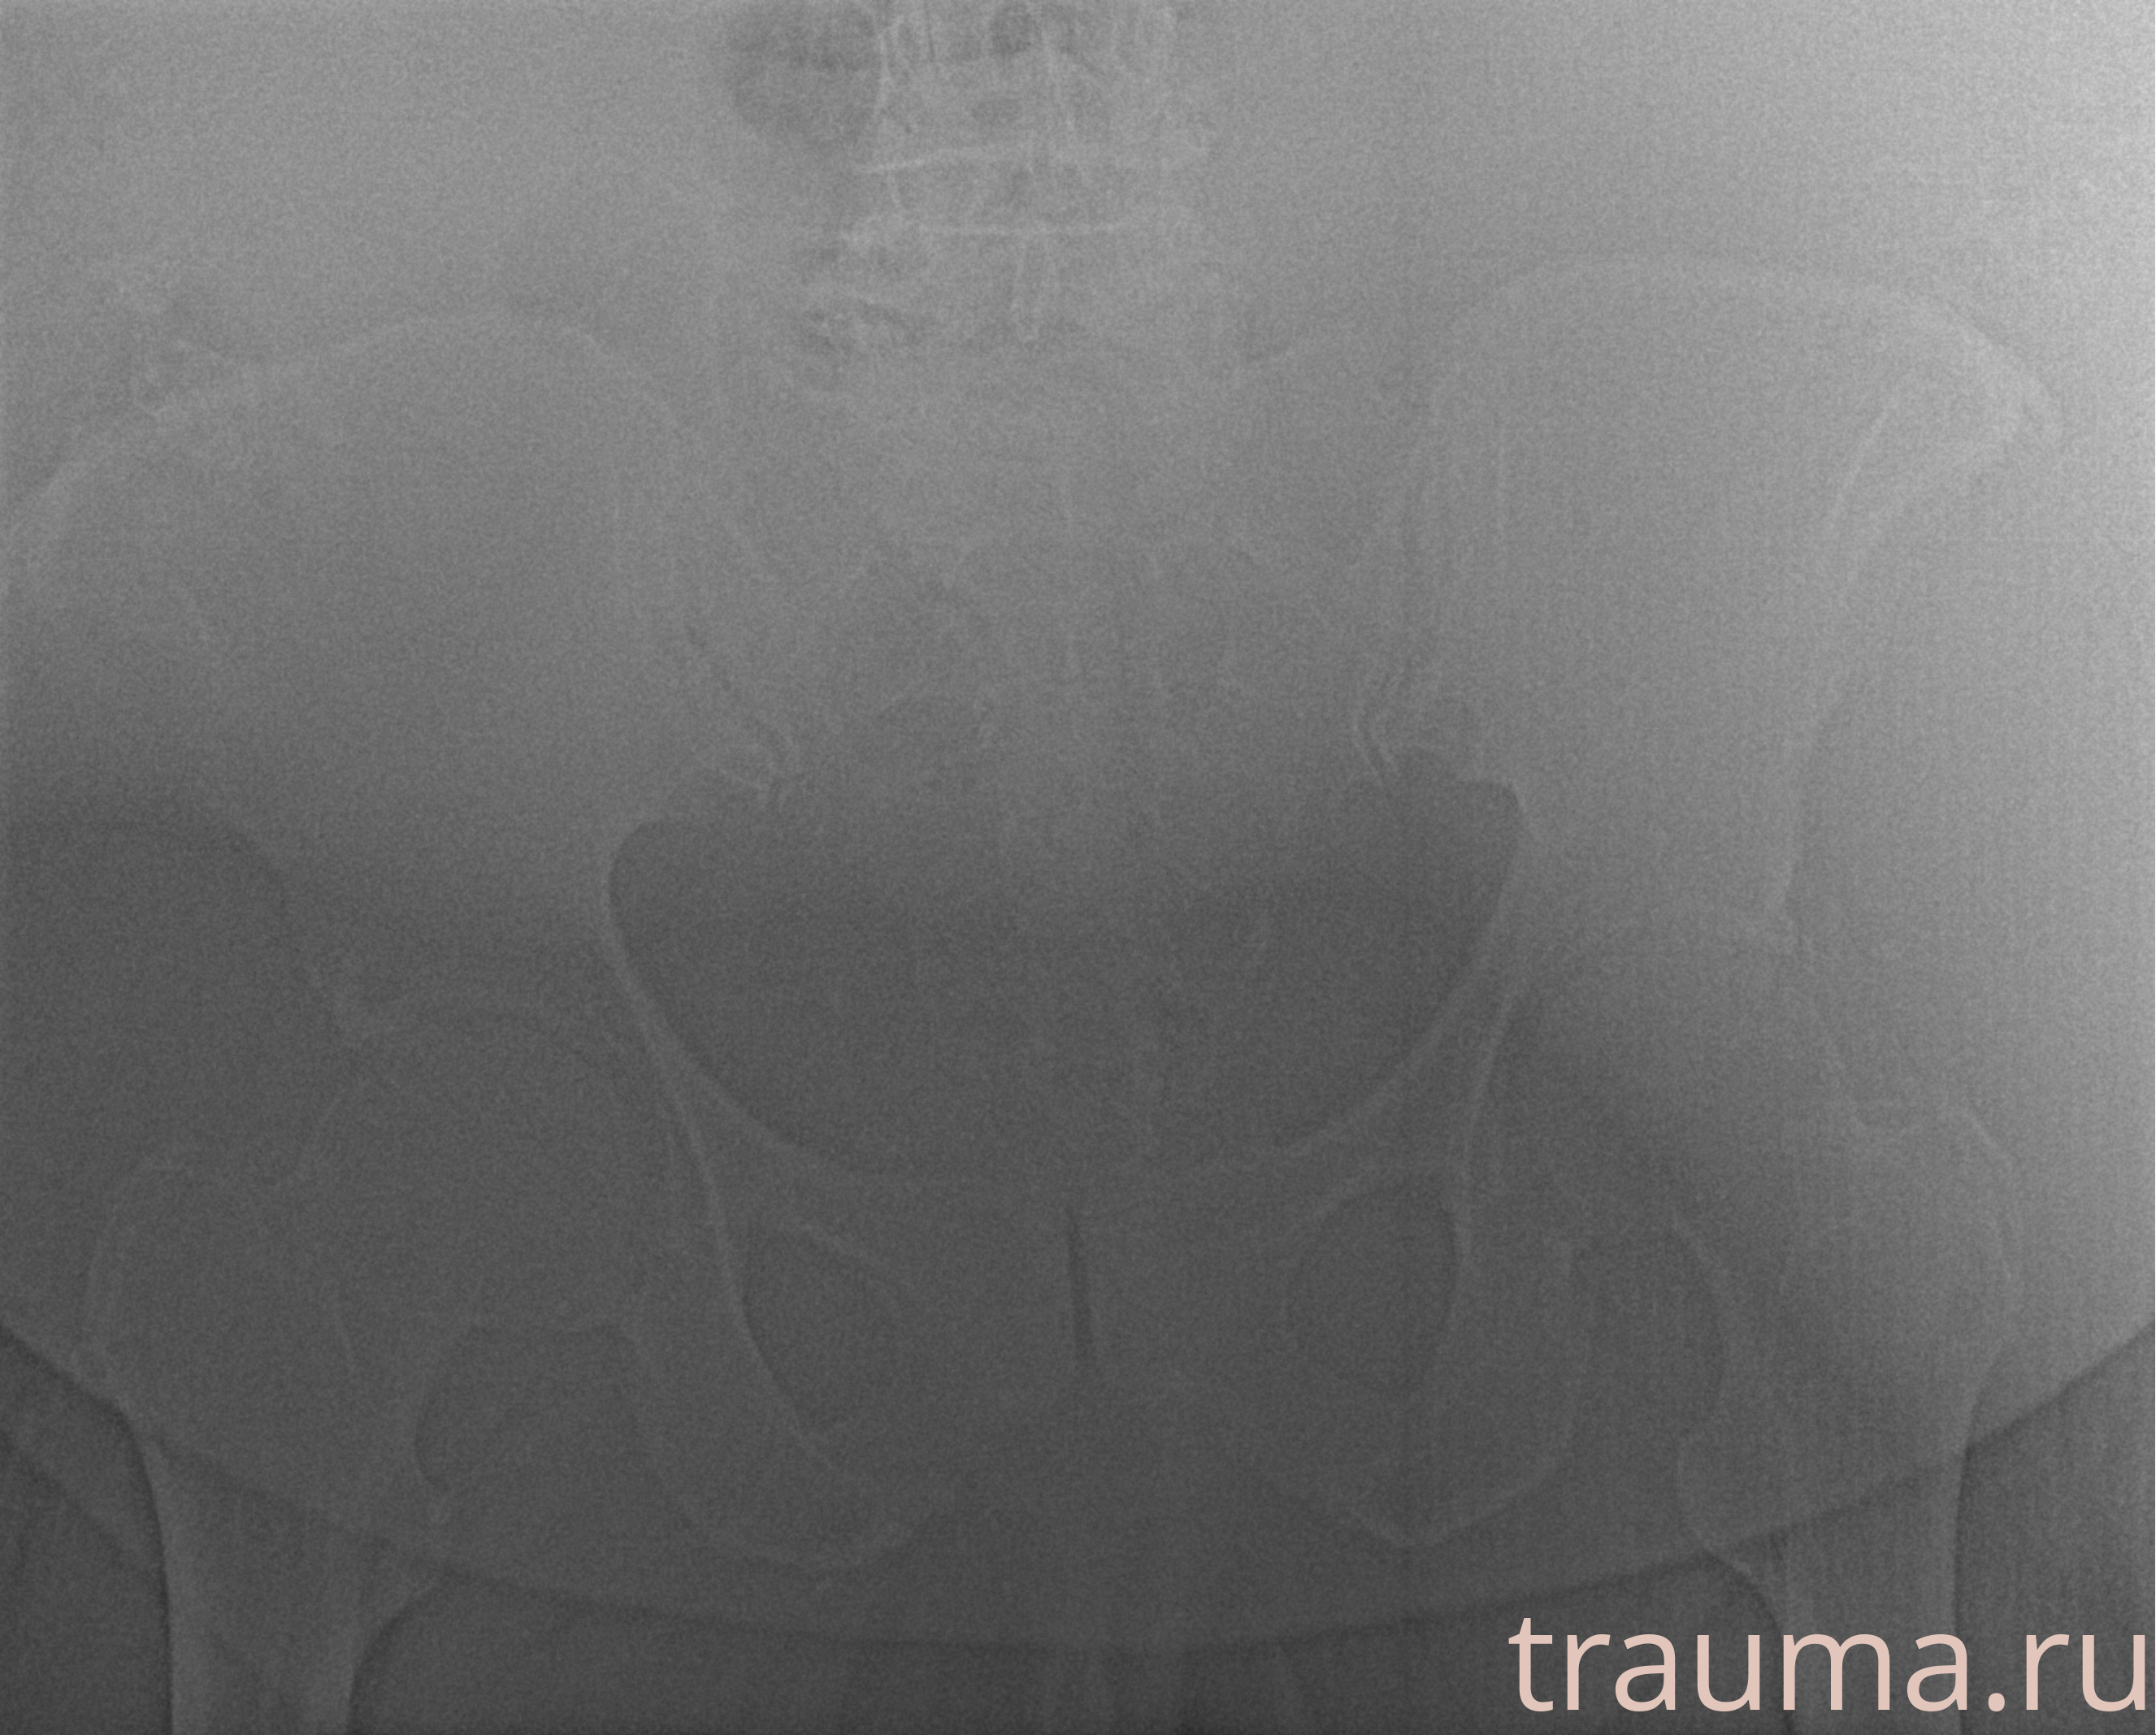

Рентген на дому: по вашему адресу приезжает врач-рентгенолог, травматолог-ортопед с мобильным рентгеновским аппаратом, проводит диагностику травмы или заболевания, делает необходимые рентгенограммы, дает рекомендации по дальнейшему лечению. Получить качественные снимки в домашних условиях возможно благодаря уникальной методике, разработанной МосРентген Центром для института  Склифосовского